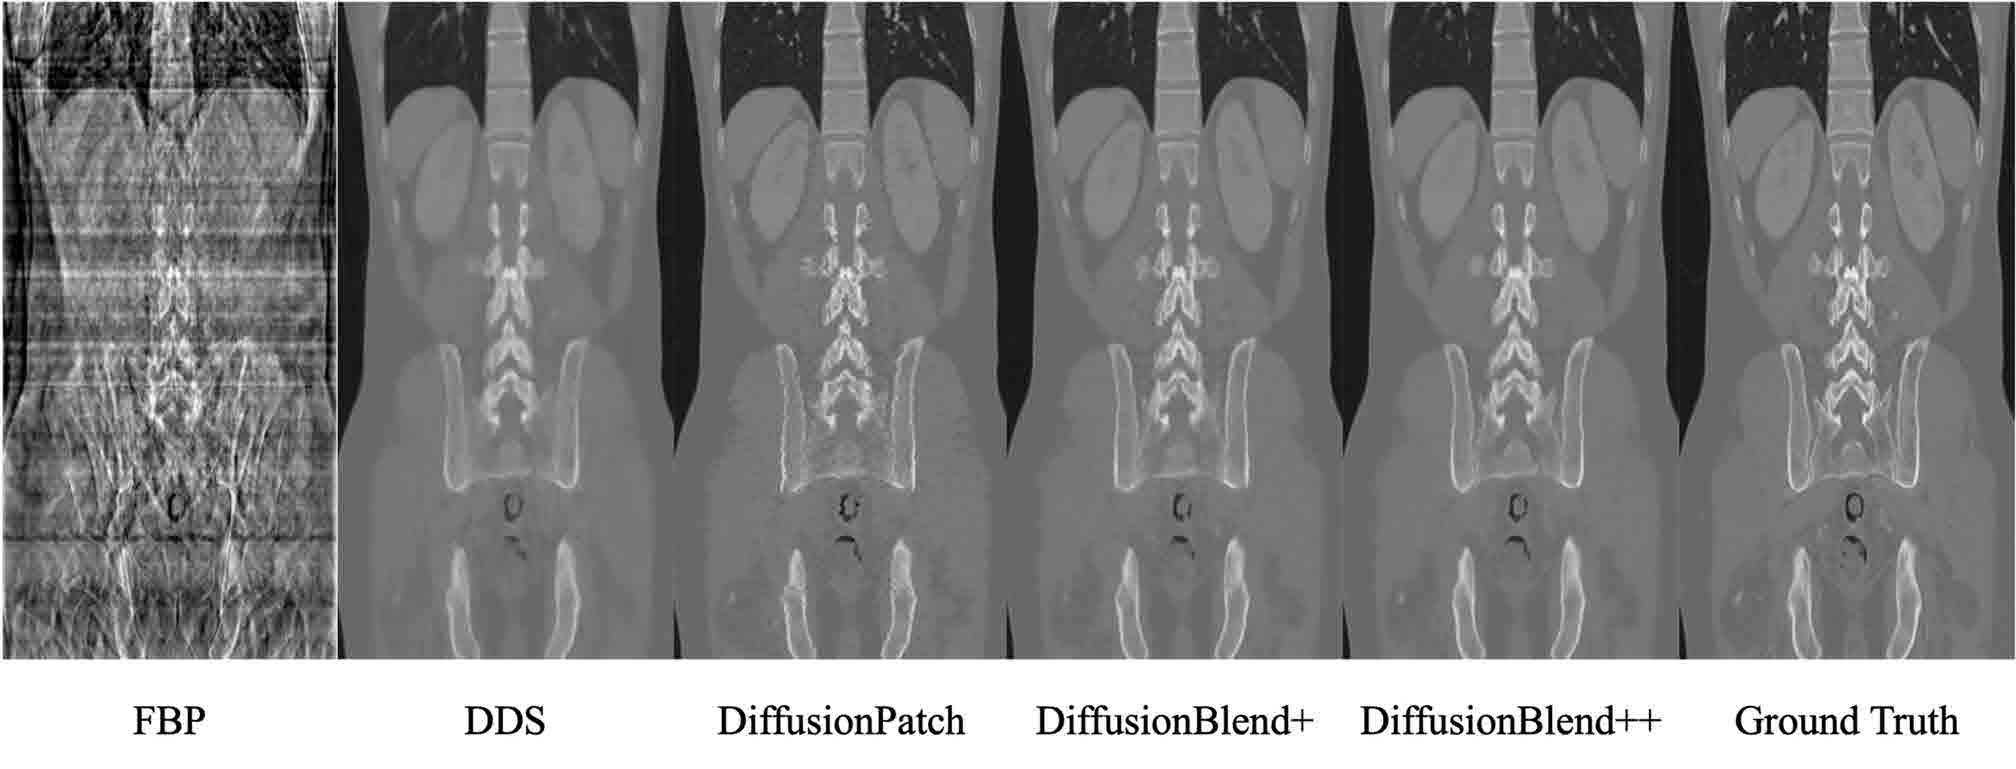

Profs. Jeff Fessler and Liyue Shen led the development of a safer way to do 3D scans using a technique they’ve dubbed DiffusionBlend. DiffusionBlend captures just 100 or even fewer X-ray projections, drastically reducing radiation exposure.

“Our new method improves speed and efficiency as well as reconstruction quality, which is crucial for medical imaging,” said doctoral student Bowen Song.

DiffusionBlend works by learning the spatial correlations among a group of nearby 2D image slices, called a

3D-patch diffusion prior, and then blends the scores of the multi-slice patches to model the entire 3D CT image volume.

“Up to this point, the memory requirements and low computational efficiency of diffusion models have limited practical application. Our approach overcomes these hurdles,” said Shen.

In addition, acceleration methods sped up the DiffusionBlend CT reconstruction time to one hour, while previous methods took up to 24 hours. They were also able to suppress visual artifacts.

“We’re still in the early days of this, but there’s a lot of potential here. I think the principles of this method can extend to four dimensions, three spatial dimensions plus time, for applications like imaging the beating heart or stomach contractions,” said Fessler.